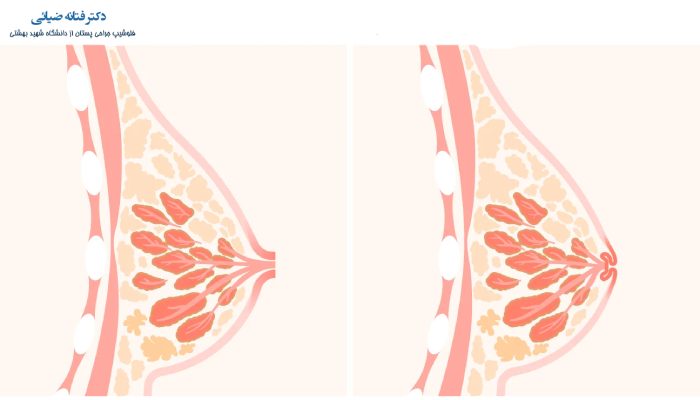

- با بالا رفتن سن و ورود به دوران یائسگی به مرور زمان مجاری شیری کوتاه شده و در نتیجه نوک سینه را به داخل می کشد.

- یکی از دیگر دلایلی که می تواند سبب وارونه شدن نوک سینه شود، آسیب یا صدمه دیدن سینه است که ممکن است در نتیجه این آسیب داکت ها و مجاری شیری سینه دچار آسیب شده و نوک سینه را به داخل بکشد.

- گاهی اوقات به دلیل اینکه به صورت مادرزادی رشد کاملی در قاعده سینه، مجاری و داکت های شیری صورت نمی گیرد برخی از افراد با مشکل نوک سینه وارونه رو به رو می شوند.

- در برخی از خانم های با سنین بالاتر از 45 سال، ممکن است مجاری شیری مسدود شده و ضخیم شوند و همین مسئله سبب التهاب، قرمزی و خروج ترشحات و فرورفتگی نوک سینه شود.

- در صورتی که فرد به سرطان پستان مبتلا باشد، علاوه بر فرورفتگی نوک پستان، تغییر شکل و وجود توده در سینه و نیز ترشح از نوک پستان را مشاهده خواهد کرد.